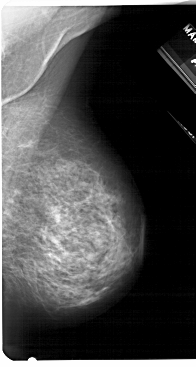

A_1279_1.LEFT_MLO

LEFT_MLO LINES 5176 PIXELS_PER_LINE 2731 BITS_PER_PIXEL 12 RESOLUTION 43.5 OVERLAY